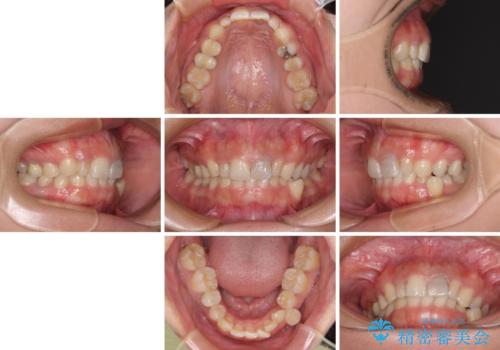

- 下顎の歯列から飛び出した小臼歯を気にして来院された患者様です。

歯列以外に、上顎左右側切歯が矮小歯であり、上顎4前歯は失活していたため、矯正治療で歯列を整えるとともに上顎前歯の幅を調整し、矯正治療後にオールセラミッククラウンにて審美歯科治療を行うこととしました。

矯正治療は、小臼歯1本分を歯列に納めないいけない状態であったため、表側のワイヤー装置にて行うこととしました。